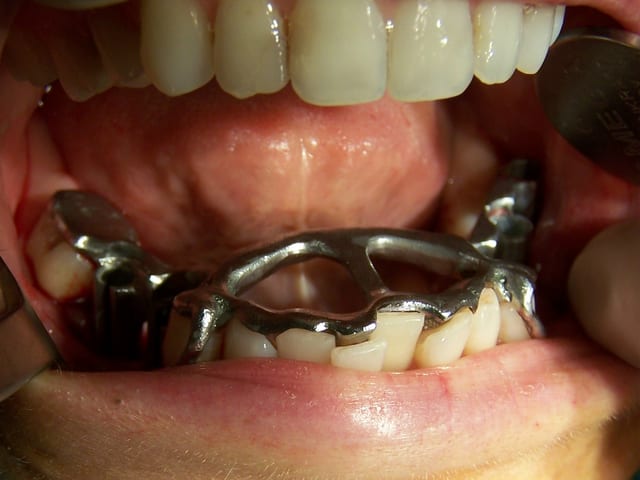

en vue indirecte

Posit la photo en bouche est pas terrible, manque de profondeur de champ, teinte...

seul les cols implantaires sont nettes

tu peux faire mieux vu la qualité de tes copies d'écran